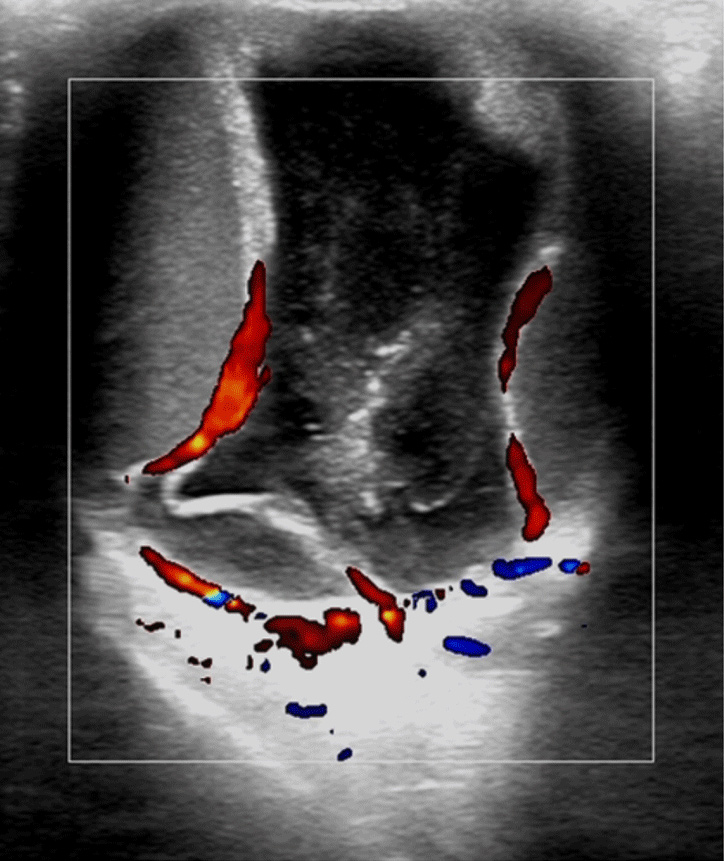

在为眼科医生提供血流信息上,彩色多普勒超声拥有无可比拟的优势,让病变组织无所遁形。

正常眼的二维 B 超图

彩色多普勒血流图

脉冲多普勒频谱图

对眼内及眼眶病变的血流观察,提供各血管血流参数的定量测量,对帮助眼科医生更好地诊断视网膜脱离、脉络膜脱离、眼内肿瘤、眼眶肿瘤、眼眶血管性病变等疾病助力极大。

彩色多普勒血流图能更好地

帮助眼科医生判断眼内膜样病变